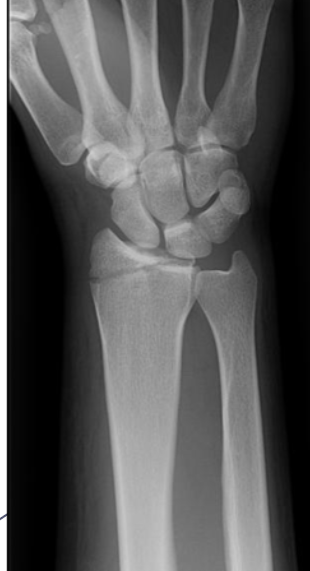

Quais fraturas tem relação com a queda com a mão estendida (FOOSH)?

Fratura do escafóide

Fratura de Colles

Fratura de Monteggia

Fratura de Galeazzi.